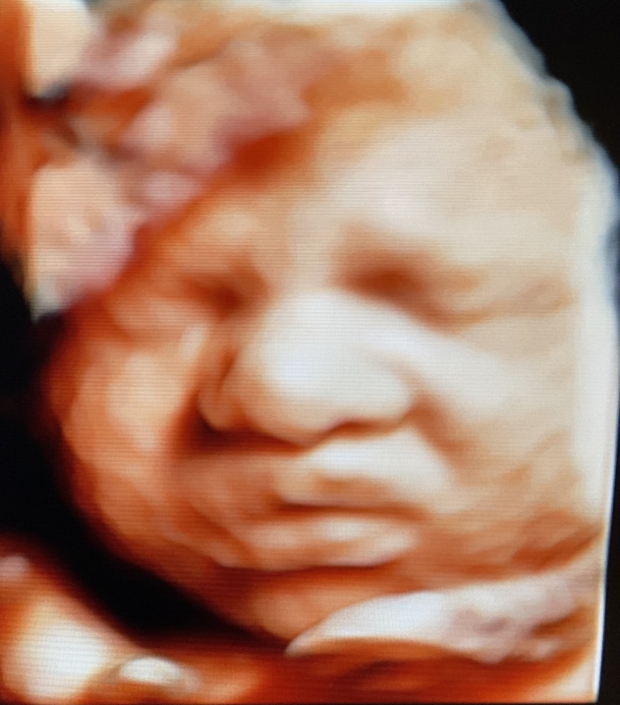

Prenatal Peek®

Prenatal Peek is the leader in 3D 4D Ultrasound. We employ only Certified / Registered Sonographers maintaining unsurpassed standards in 3D ultrasound. You deserve the best! Call us today.